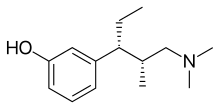

The pharmacodynamic response to an opioid depends upon the receptor to which it binds, its affinity for that receptor, and whether the opioid is an agonist or an antagonist. For example, the supraspinal analgesic properties of the opioid agonist morphine are mediated by activation of the μ1 receptor; respiratory depression and physical dependence by the μ2 receptor; and sedation and spinal analgesia by the κ receptor. Each group of opioid receptors elicits a distinct set of neurological responses, with the receptor subtypes (such as μ1 and μ2 for example) providing even more [measurably] specific responses. Unique to each opioid is its distinct binding affinity to the various classes of opioid receptors (e.g. the μ, κ, and δ opioid receptors are activated at different magnitudes according to the specific receptor binding affinities of the opioid). For example, the opiate alkaloid morphine exhibits high-affinity binding to the μ-opioid receptor, while ketazocine exhibits high affinity to ĸ receptors. It is this combinatorial mechanism that allows for such a wide class of opioids and molecular designs to exist, each with its own unique effect profile. Their individual molecular structure is also responsible for their different duration of action, whereby metabolic breakdown (such as N-dealkylation) is responsible for opioid metabolism.

Tramadol and tapentadol, which act as monoamine uptake inhibitors also act as mild and potent agonists (respectively) of the μ-opioid receptor.[264] Both drugs produce analgesia even when naloxone, an opioid antagonist, is administered.[265]